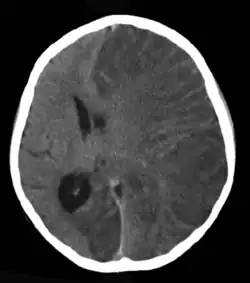

Estima-se que o traumatismo cranioencefálico (TCE) seja responsável por 6% a 20% dos casos de epilepsia, dependendo da gravidade, mecanismo e população estudada. Lesões cerebrais leves dobram o risco, enquanto TCEs graves aumentam o risco em cerca de sete vezes. Em vítimas de ferimento craniano por arma de fogo de alta energia, o risco pode chegar a 50%.[58] O AVC é uma causa importante de epilepsia, especialmente em adultos mais velhos.[59] Aproximadamente 6% a 10% das pessoas que sofrem um AVC desenvolvem epilepsia, geralmente nos primeiros anos após o evento. O risco é mais alto em AVCs graves que envolvem regiões corticais, especialmente nas hemorragias intracerebrais.[60] Entre aqueles com tumores cerebrais, quase 30% têm epilepsia, tornando-os a causa de cerca de 4% dos casos. O risco é maior para tumores no lobo temporal e aqueles que crescem lentamente.[61]

A neuroimagem, geralmente por ressonância magnética (RM), é recomendada para investigar causas estruturais da epilepsia. Quando a RM for contraindicada ou indisponível, pode-se considerar a tomografia computadorizada (TC). A interpretação deve ser feita por radiologistas com experiência em epilepsia.[80]